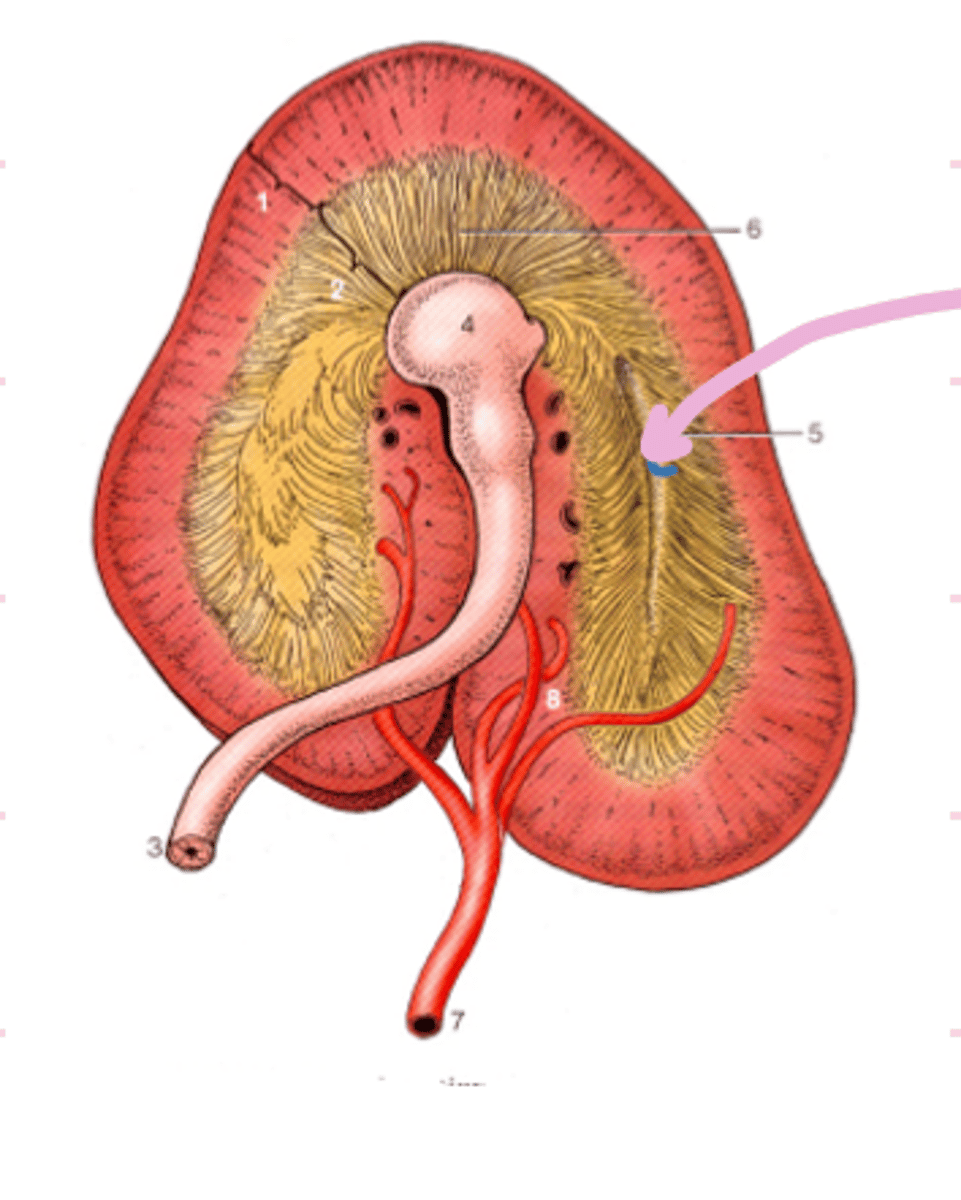

Knowing that the cecum base is in the caudal part of the right abdomen, we know that:

-Picture Left = Horse right

-Picture Right = Horse Left

-Picture top = Cranial

How would you orientate yourself to interpret this picture? Label right, left, and cranial

Apex of cecum

What is the name and portion of the organ labeled A?

4

How many bands does structure A have?

Left ventral Colon

What specific segment of the ascending colon is labelled B?

Pelvic flexure

Ingesta leaving section B would go through what flexure next?

dorsal diaphragmatic flexure (diaphragmatic flexure)

What is flexure C?

What is B?

3 bands in left/right dorsal colon

How many bands does C have?

transverse colon

ingesta leaving C will travel through what impaction site?

terminal recess

What is indicated by arrow?